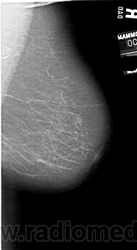

Со старением железистая ткань постепенно исчезает: прозрачность жировой ткани становится преобладающей с несколькими каркасами, связанными с опорными волокнистыми структурами.

Жирная (не плотная) грудь

Умеренно плотная грудь

Плотная грудь

Маммограммы представляют собой изображения структур, проецируемых на плоскость: плотная грудная маммограмма, следовательно, состоит из многих других структур, которые необходимо проанализировать, чем более жирная, пустая грудь. По этой причине диагностировать рак молочной железы труднее для моложе, чем для пожилых женщин.

Нажмите на миниатюрные картинки, чтобы получить увеличенный размер.